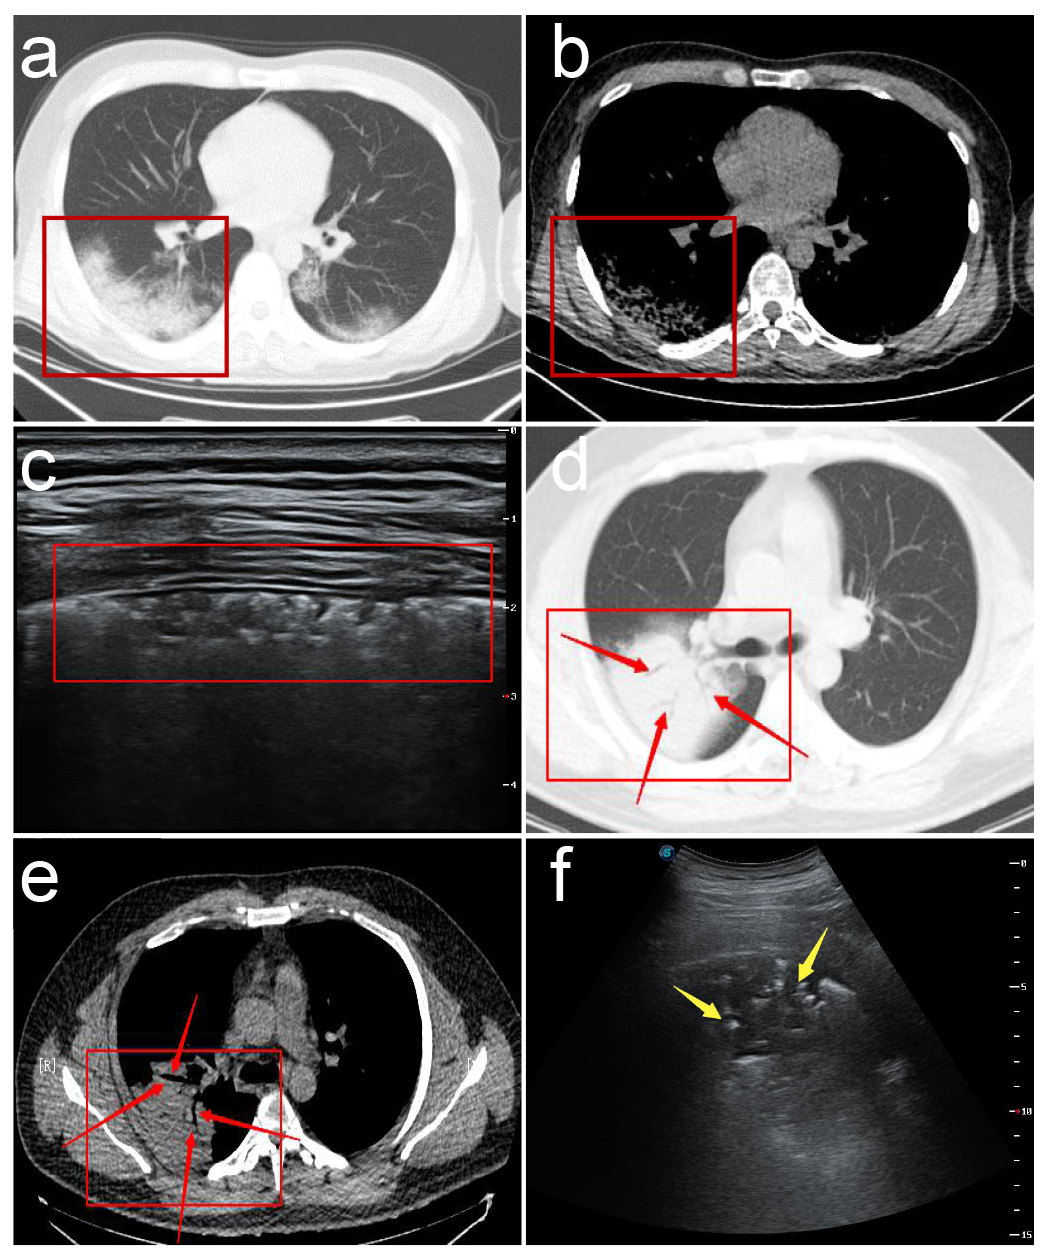

这项研究为2020年1-2月份在西安市胸科医院收治经临床确诊的非重症期新型冠状病毒肺炎(COVID-19)患者共20例,均行常规二维超声及彩色多普勒超声检查,观察病灶在超声影像学下的图像特征。

主要观察内容:(1)胸膜线是否光滑、连续是否中断;(2)双肺肺周"B"线分布位置,数目,是否融合;(3)如有肺周病灶应观察病变回声、部位、形态、范围;(4)如有实变观察其内是否有支气管充气征,或细支气管肺泡充气征;(5)应用彩色多普勒超声技术了解实变肺部病灶血流分布等;(6)胸膜下病灶周围是否出现胸腔积液,胸膜是否出现局限性增厚,有无胸腔积液。

1.病灶部位多分布于双肺后野区。

2.超声探查可见胸膜线下多条不连续或连续融合B线(瀑布征),或弥漫性B线(白肺征),同时A线消失。与心源性肺水肿所致B线比较,冠肺B线融合现象更普遍,位置相对也比较固定,B线边缘模糊,无分叉征,起点位于胸膜下病灶较肺水肿B线起点圆钝(凸阵探头)。

3.高频超声显示胸膜线欠光滑、毛糙,连续性中断,主要是由于胸膜下肺泡及间质病变气体含量减少,声波反射减少所致。

4.胸膜下病灶可见多发小斑片样实变,长条样实变。

5.病灶内回声均匀或不均匀,多可见细小支气管肺泡充气征(早期、进展期多见。考虑次级肺小叶受间质炎性侵犯,间质水肿增厚,部分细小支气管及肺泡尚未受侵犯气体含量高所致)或支气管充气征(重症期或局部大片实变多见,考虑原因可能为局部炎症风暴所致大部细小支气管肺泡水肿实变仅留较大支气管或部分肺泡所致伴病灶后弥漫性B线,经观察部分发病时间较长病情趋于好转冠肺患者CT影像呈小结节样实变影,超声亦可见胸膜下结节样不规则回声影,后见融合B线,位置固定。

6.高频超声还可显示病变肺周的胸膜局限性增厚及胸膜下病变周围局限胸腔积液(线阵探头更清晰多数患者胸膜增厚约1-2mm,病灶周胸腔内局限性胸膜下积液约2-3mm)随病情进程有所变化。

7. CDFI超声显示非重症期新型冠状病毒肺炎(COVID-19)患者胸膜下实变病灶血流信号不敏感,随更换多台不同品牌新型超声仪器仍显示呈乏血流表现,具体原因可能与病变的病理性质有关,同时与病变进展时期有关,但应引起高度重视,因普通炎症所致肺实变彩色多普勒超声显示呈丰富血流信号,一般预后较好但新型冠状病毒肺炎(COVID-19)患者病变一般进展迅速,引起患者死亡,是否与肺组织未能迅速建立起丰富微小血管交换机制相关还有待于进一步研究,但值得肯定的是彩色多普勒超声相比其他医疗设备更能有效直观的了解实变肺组织血供信息,对临床医生预先判断患者预后及病情进程有重要的临床价值。